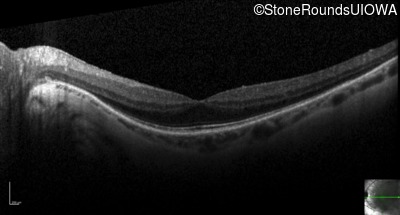

Optical Coherence Tomography - Left - 20/16 -1

Exemplar / OCT Stack